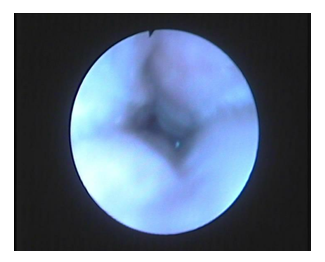

Figure 6 Partial supraglottic obstruction due to flappy epiglottis.

Figure 7 Complete supraglottic obstruction due to flappy epiglottis.

Regarding presence or absence of flappy epiglottis there was a slight difference that was statistically insignificant (Table 5).

Only 13.6% (n=9/66) of our patients showed supraglottic obstruction due to flappy epiglottis while Eichler C et al.,25 found 32.0% (n=31) with an obstruction at the epiglottis level. Results reported by other groups varied substantially between 1% and 40%.26‒28 Thus, the frequency and distribution of the different levels of obstruction in our study population is comparable to those of other groups.